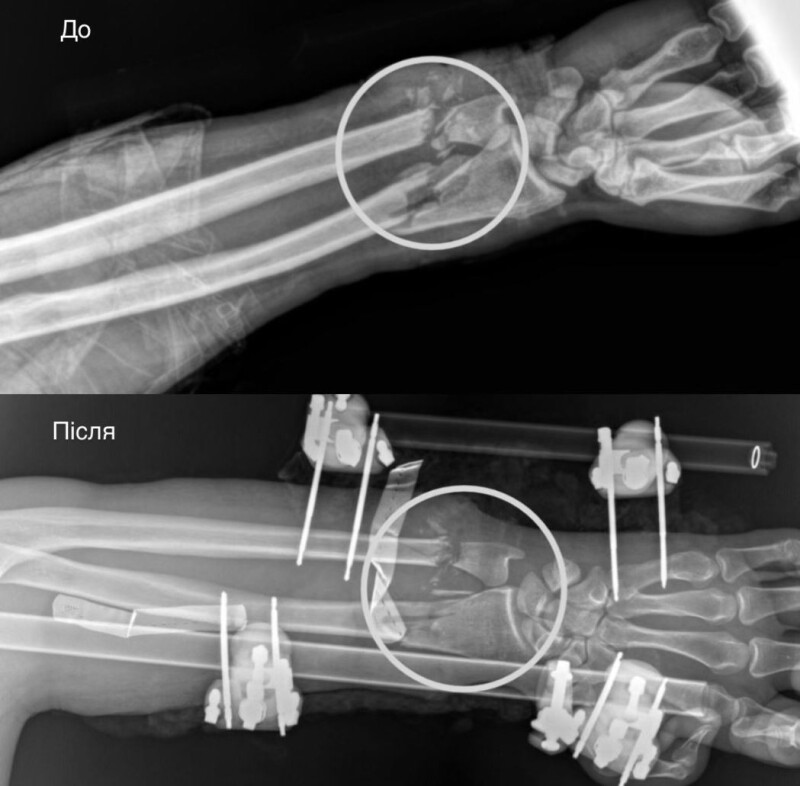

Рука «до» і «після» операції.

Першими свою роботу в операційній виконали ортопеди-травматологи. Вони стабілізували переламані кістки передпліччя за допомогою апарата зовнішньої фіксації. Після чого вже судинні хірурги взялися відновлювати кровопостачання. Цей етап був вирішальним, адже без циркуляції крові тканини б швидко змертвіли. Однак, на щастя, хірургам вдалося успішно зшити судини.

Під час третього етапу хірурги зайнялися вже м’якими тканинами. Аби відновити згинально-розгинальну функції руки, вшили пошкоджені сухожилля і м’язи. А нерви підготували до подальшої операції, яка відбудеться через місяць–два. Завершилося це багатоетапне втручання аутодермопластикою, під час якої реконструктивні хірурги закрили дефект власною шкірою пацієнта.